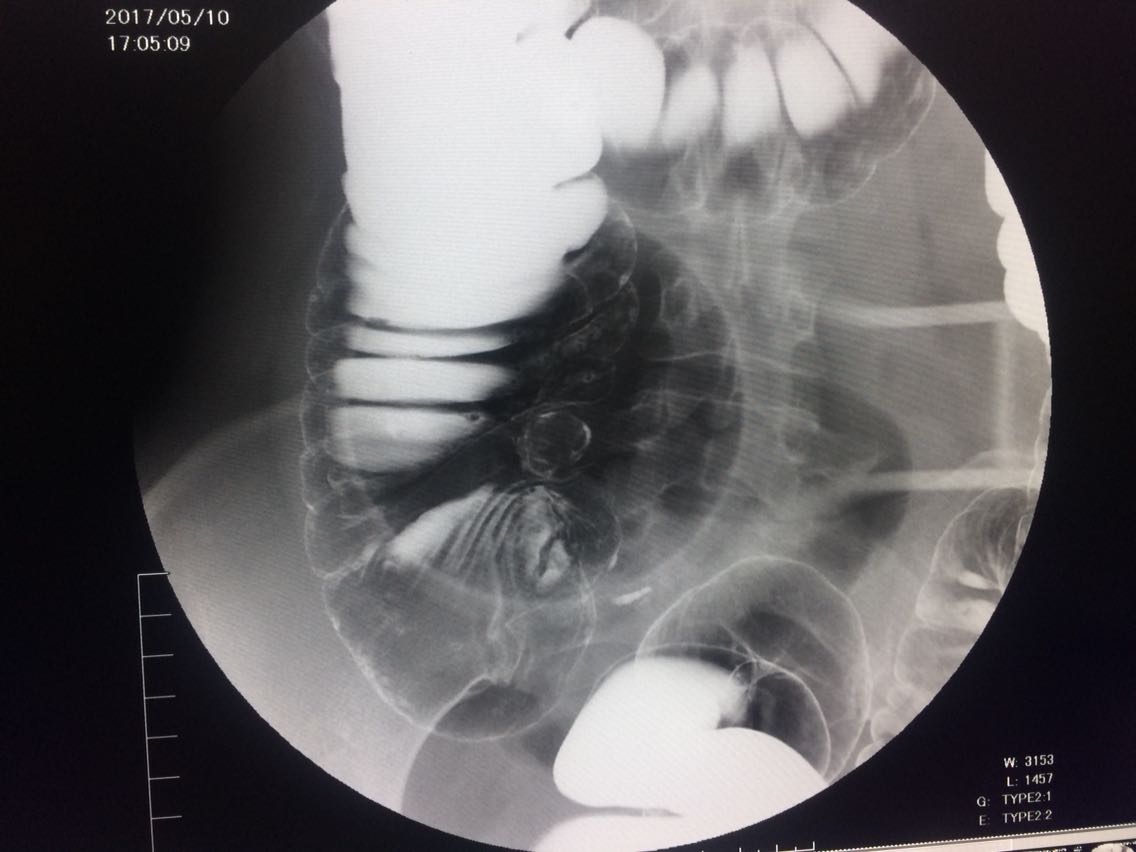

间断右下腹疼痛6年余。 6年来,无诱因出现右下腹痛,间断发生,呈胀痛,可忍受,压痛,无反跳痛。 既往:3年前,做肠镜未见明显异常。

查体,右下腹压痛。 入院做钡灌肠造影。

考虑升结肠占位。 完善术前各项检查。手术治疗。